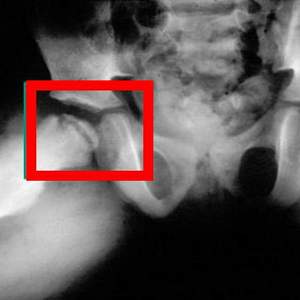

Рентгеновские снимки обычно показывают перелом или повреждение головки бедра. Типичное проявление – уплощение головки, потеря округлой формы.

Однако рентген на ранних стадиях заболевания редко выявляет патологию до того, как поврежденная костная ткань не начинает разрушаться.

Диагностику рекомендуют проводить каждые несколько месяцев, чтобы увидеть процесс развития и инволюции патологии.

- Рентген показывает состояние кости головки бедренной кости для определения стадии заболевания.